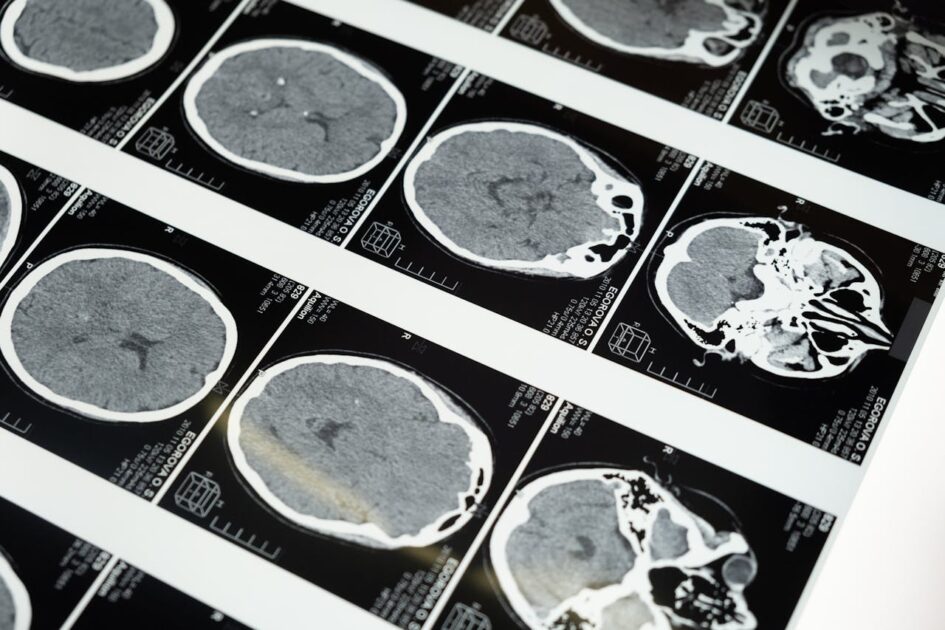

Según el parte médico, el cantante español “presenta un linfoma cerebral primario con dos nódulos cerebrales, en el hemisferio izquierdo. Estos justifican los síntomas neurológicos que presentó hace unos días”.